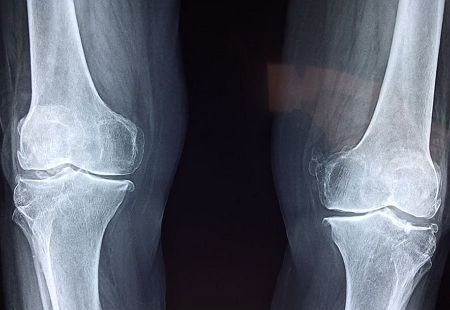

첫번째 비타민D 효능 - 골다공증의 예방

우리의 몸에 비타민 D와 칼슘이 오랜기간 부족하게 되면 뼈는 약해지고 쉽게 부러지게 됩니다. 이러한 상태를 골다공증이라고 하는데요, 나이가 들수록, 그리고 남성보다는 여성의 경우 발생할 위험이 높습니다.

또한 비타민 D가 부족해지면 근육이 약해지고 통증이 쉽게 생길 수 있습니다. 이는 신체의 균형과 낙상을 초래할 수 있기 때문에 결국 뼈건강에 악영향을 미칠 수 있습니다. 그러므로 뼈의 강도를 유지하고 골다공증을 예방하기 위해서는 적절량의 비타민 D와 함께 칼슘을 꾸준히 섭취해 주는 것이 좋습니다.